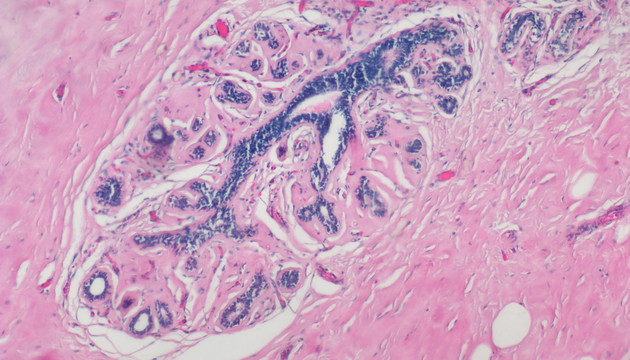

依据癌细胞在分子表达层面和细胞组织层面的变化,运用各类显微成像技术对癌细胞进行筛选与识别,如①病理切片②免疫组化(IHC)③原位荧光杂交(FISH)④循环肿瘤检测(CTC)⑤肿瘤细胞培养研究

癌症研究中的成像有明场和荧光两类,明场设备要求低,但病理切片全片判读工作量大,效率低,使用切片扫描系统通过电动扫描和拼接软件,实现高效全局成像与局部放大,可提升诊断精度与效率;多色荧光成像高灵敏度、高特异性,但信号弱,需优化激发光、滤光片、成像设备及图像处理,以获取清晰多通道信号;对于细胞培养,还有如何长时间成像监测,同时减少污染、不影响细胞生长的困难